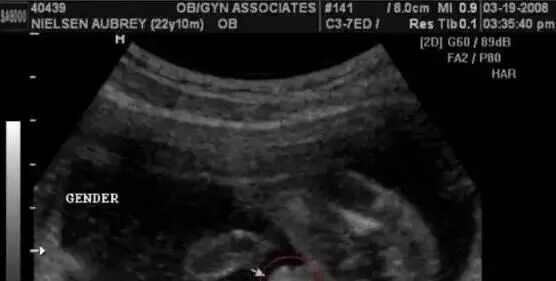

第一种:在彩超单上会印,顶头最右边有两行字,是英文字母和数字组成的,第一行是日期,第二行是时间,如果第一行是M开头,那就是male男,如果是F开头就是female女,第二行打头的T是时间的意思。

第二种:四维彩超单上很小英文字母Qual high: 1是女孩,2是男孩。

第三种:通过四维彩超图看清胎儿性别